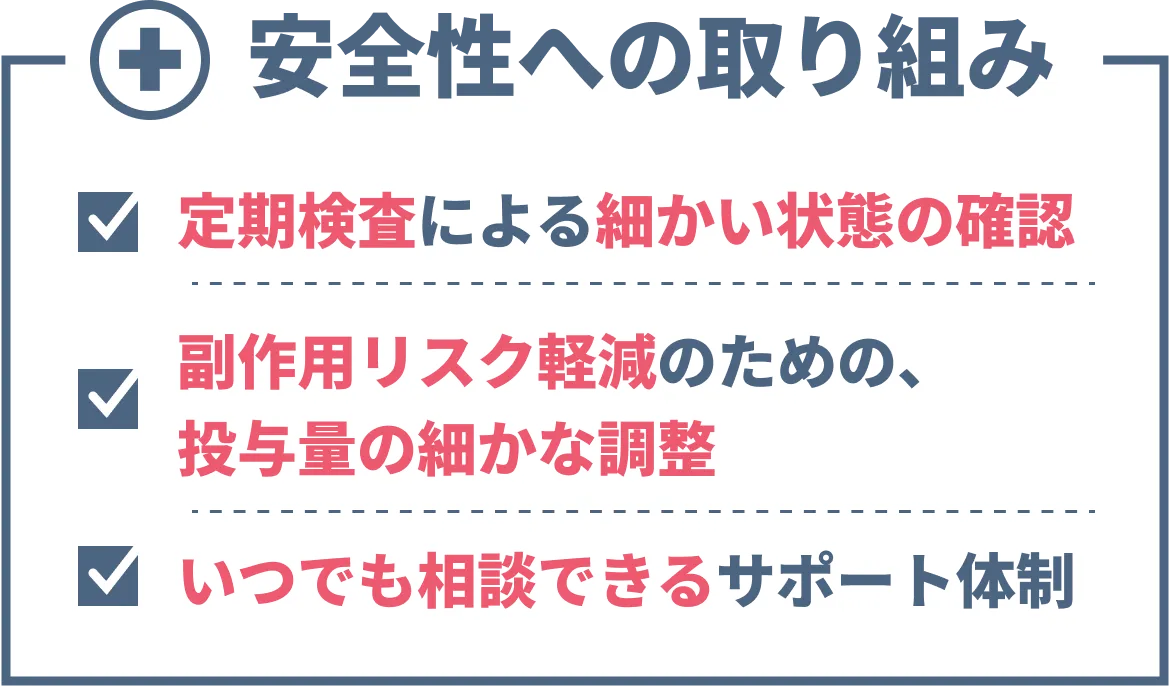

現時点では大きな副作用はあまり認められていませんが、医師の管理の元で細心の注意を払う必要があります。